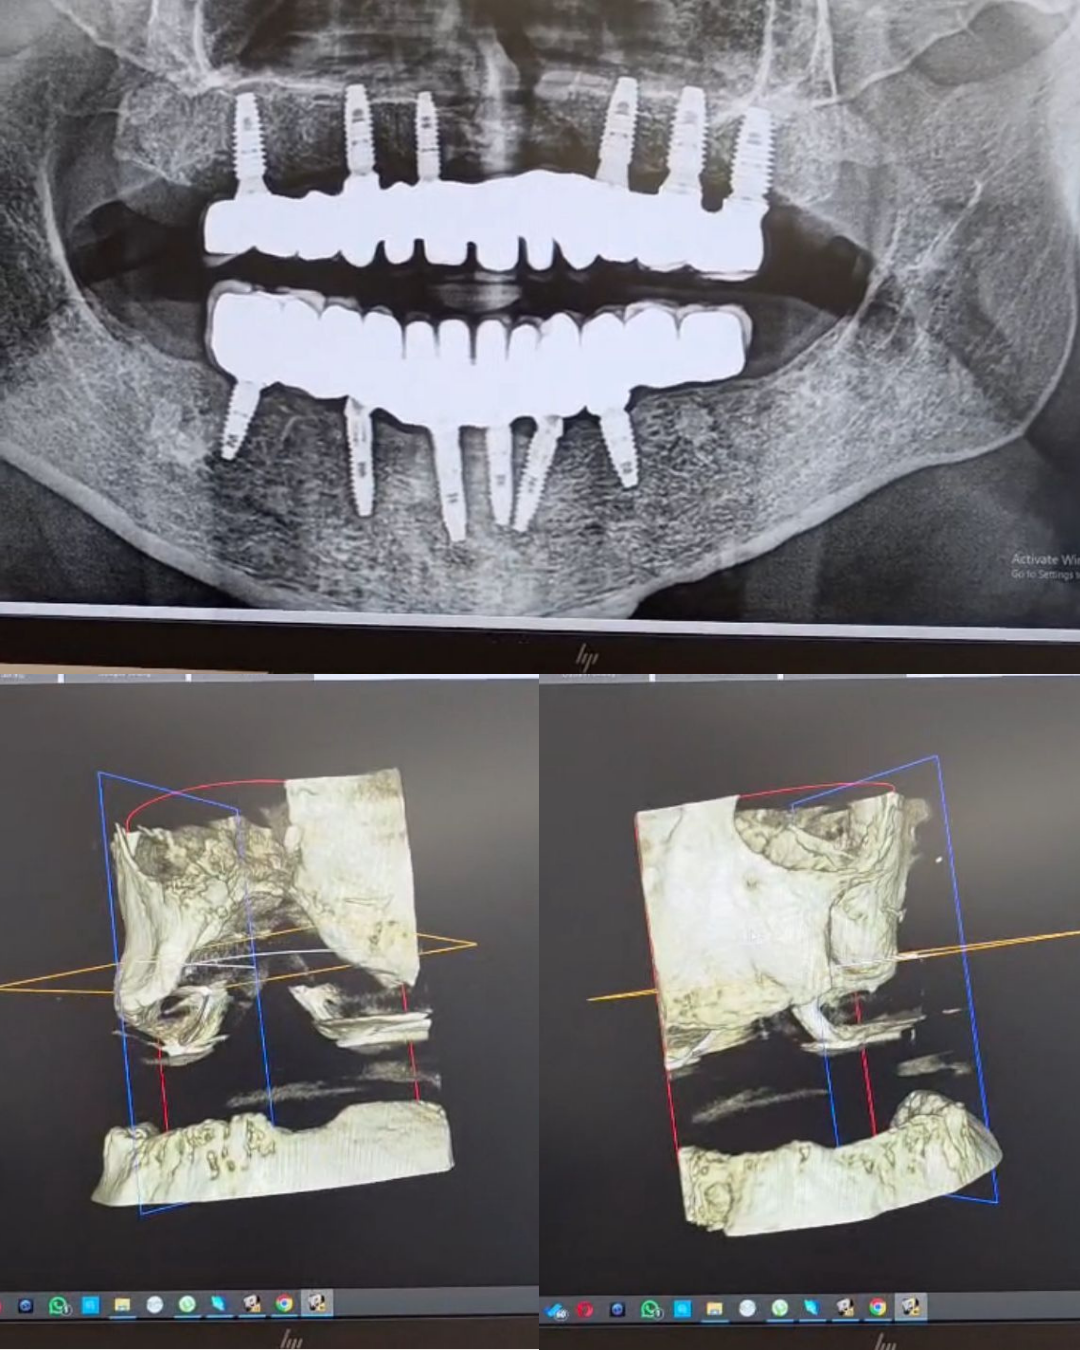

Diagnoza: teknologjia si bazë e vendimmarrjes klinike

Përpara çdo vendimi terapeutik, ekipi i Ekdent ndoqi një protokoll të plotë diagnostik:

• Skaner 3D (CBCT) për vlerësimin e volumit dhe densitetit kockor

• Grafi panoramike për një pasqyrë të përgjithshme të strukturave anatomike

• Analizë e kujdesshme e defektit kockor dhe indeve përreth

Këto ekzaminime ishin vendimtare për të kuptuar se rasti nuk mund të zgjidhej me zgjidhje të thjeshta apo standarde. Ishte e nevojshme një strategji e personalizuar dhe e ndërtuar në faza.

rehabilitim total oral mbi implante Pas analizës së plotë, u vendos të realizohej një rehabilitim total i kavitetit oral me: 6 implante dentare në nofullën e sipërme 6 implante dentare në nofullën e poshtme Kurora definitive të mbështetura mbi strukturë të qëndrueshme metalike Ky plan synonte jo vetëm zëvendësimin e dhëmbëve, por rikthimin e funksionit mastikator, stabilitetit, të folurit dhe mbylljen e komunikimit oronazal.